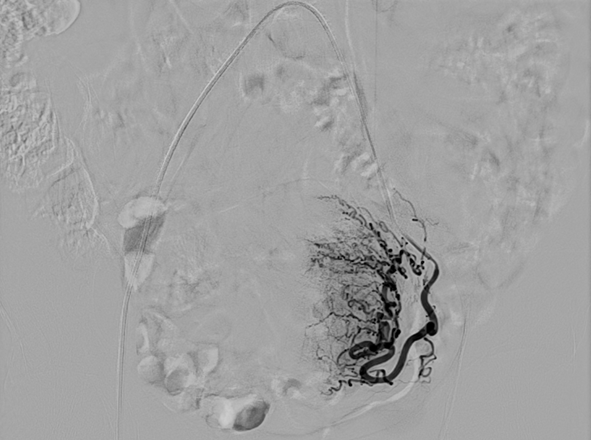

这个方法,原理很直接,可以理解为一次精准的“断供”:子宫和那些“跑错地方”的组织,都需要通过子宫动脉来供应血液和营养。医生会在大腿根部找一个像打针一样的小口,放进去一根非常细的软管。在清晰的影像引导下,这根管子能准确地找到给子宫供血的血管。通过这根管子,医生会注入无数个极其微小的颗粒。这些颗粒会堵住为那些“问题组织”供血的小血管。失去了血液供应,那些在肌肉里“捣乱”的组织就会因为“缺粮”而慢慢萎缩、被身体吸收掉。正常的子宫组织有其他血管供血,一般不会受影响。这样,子宫会慢慢变小变软,症状也就减轻了。